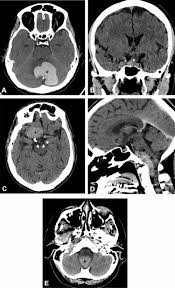

Correlation Of Radiological Features Of White Epidermoid Cysts With Histopathological Findings Scientific Reports

Computed Tomography Of The Abdomen And Pelvis Revealing A Massive Download Scientific Diagram